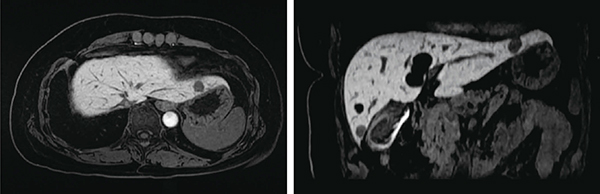

図3 DISCOによる肝ダイナミック撮像

3mmスライス,21秒呼吸停止撮像,3.9秒/phase×5phase

(画像ご提供:聖隷浜松病院様)